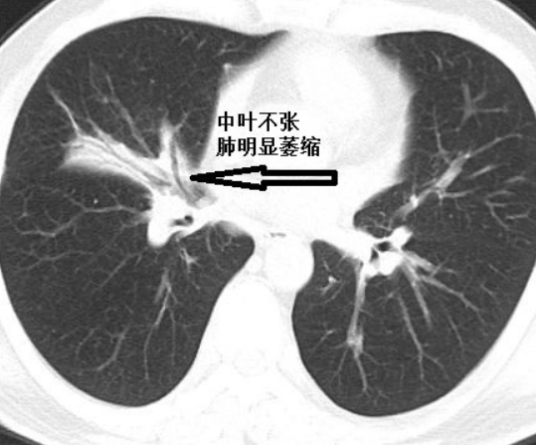

CT检查:对诊断价值更大,特别是对明确支气管腔内阻塞性病变的位置甚或性质,探查肿大的纵隔淋巴结,鉴别纵隔包块与纵隔周围的肺不张。

肺不张的直接X线征象 不张的肺组织透亮度降低,均匀性密度增高,恢复期或伴有支气管扩张时可密度不均(囊状透亮区)。不同程度的体积缩小,亚段及以下的肺不张可因有其他侧枝的通气而体积缩小不明显。叶段性肺不张一般呈钝三角形,宽而纯的面朝向肋膈胸膜面,尖端指向肺门,有扇形、三角形、带状、圆形等。2.

肺不张的间接X线征象 叶间裂向不张的肺侧移位,如右肺横裂叶间胸膜移位,两侧的斜裂叶间胸膜移位等;由于肺体积缩小,病变区的支气管与血管纹理聚拢,而邻近肺代偿性膨胀,指使血管纹理稀疏,并向不张的肺叶弓形移位;肺门阴影向不张的肺叶移位;肺门阴影缩小和消失,并且与肺不张的致密影相隔合;纵隔、心脏、气管向患侧移位,特别是全肺不张时明显,有时健侧肺疝移向患侧,而出现纵隔疝;横膈肌升高,胸廓缩小,肋间隙变窄。